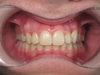

Il faut alors aller la chercher : On pause un appareil fixe multiattaches pour faire la place et servir de point d’appui pour la traction de la canine.

2e radio : Traitement multibagues avec création de l'espace pour la canine